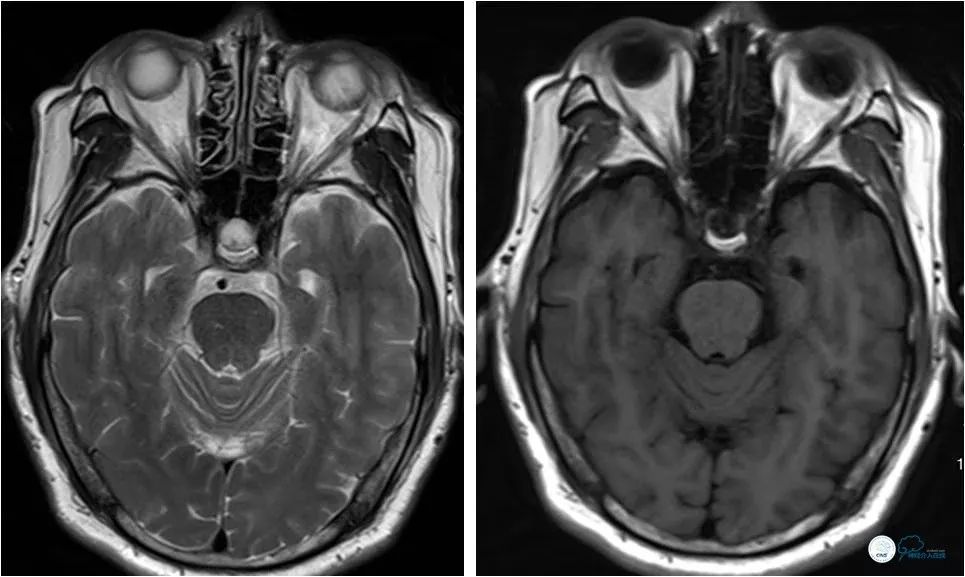

头颅MRI:桥脑散在腔隙灶(图2)。

图2